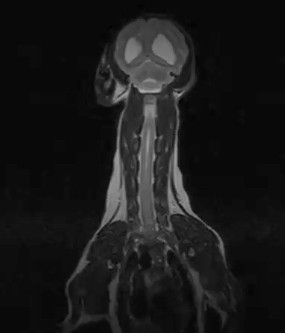

W obrębie kanału kręgowego najczęstszymi wskazaniami do badania rezonansem magnetycznym u zwierząt są:

• ocena rdzenia kręgowego, splotów i nerwów rdzeniowych

• ocena przepukliny i stopnia ucisku na rdzeń kręgowy

• dyskopatie, neuropatie, radikulopatie

• spondylomielopatia szyjna

• malformacje Chiariego

• wady złącza czaszkowo mózgowego